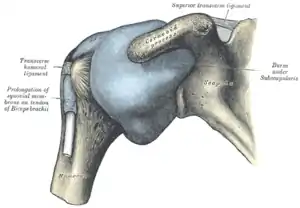

Capsule of shoulder-joint (distended). Anterior aspect. | |

Examples of this form of articulation are found in the hip, where the round head of the femur (ball) rests in the cup-like acetabulum (socket) of the pelvis; and in the shoulder joint, where the rounded upper extremity of the humerus (ball) rests in the cup-like glenoid fossa (socket) of the shoulder blade.[2] (The shoulder also includes a sternoclavicular joint.)